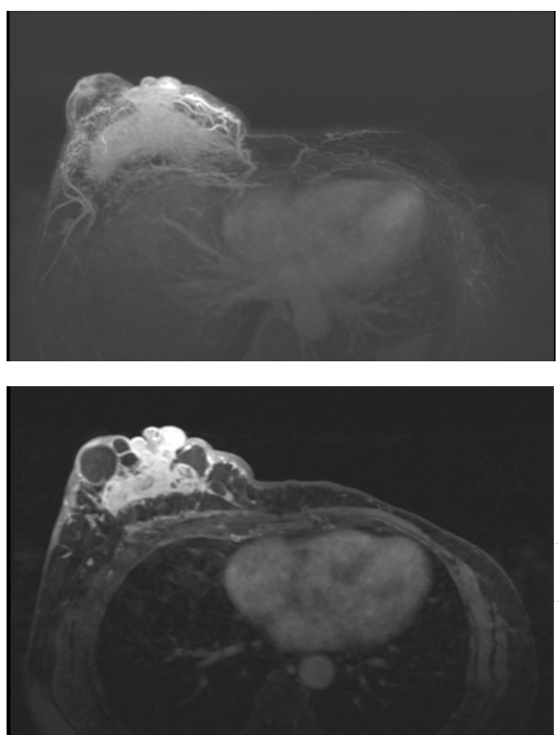

MR乳腺平扫+增强组合(3.0T):征象描述:右乳腺见不规则团片状混合信号,实性成分呈等T1稍长T2信号,DWI呈高信号,ADC呈低信号,并见多发大小不等的囊性长T1长T2信号,局部见少许短T1稍短T2出血信号,病灶边界不清,范围约56mm×91mm×74mm,增强扫描病灶实性部分明显不均匀强化,动态增强曲线呈流出型,病灶血管丰富紫乱,向前累及乳头导管及Cooper韧带,皮肤增厚、凹陷,向后局部紧贴胸壁肌层。左乳腺术后缺如。右侧腋下见数枚增大淋巴结,较大者短径约12mm,边界清楚,信号及强化均匀。

诊断意见:

右乳腺不规则肿块伴多发囊变、少量出血,符合乳腺癌,BI—RADS6类.2.右侧腋下增大淋巴结,考虑淋巴结转移可能。

辅助检查--治疗前病灶:

疗效评估:PR

本次治疗后的转归及后续策略:患者治疗期间规律在北京大学深圳医院随访复查,主管医生应用本院创新型的院后管理服务平台随访追踪:用于肿瘤疗效评估的影像学检查、肿瘤标志物的变化,血常规、肝功能、心电图等医生关注的不良反应监测指标均可在手机小程序可视化展现,并与患者进行线上沟通。截止发稿日期,该患者仍在当前治疗方案随访中,肿瘤在治疗前3个月快速退缩,疗效评估为PR,此后维持SD状态,PFS已达20个月。